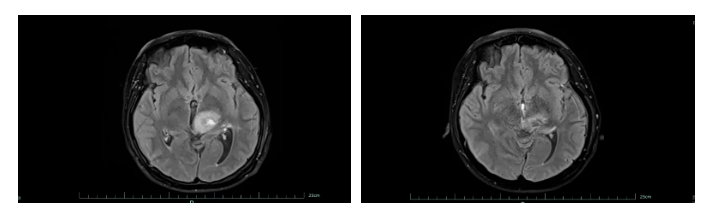

左为治疗前,右为治疗后。图片来源于稿源单位

好在经过系统治疗,黄女士的肿瘤明显缩小,病情得到有效控制。目前,她已回归正常生活和工作,生活质量显著改善。